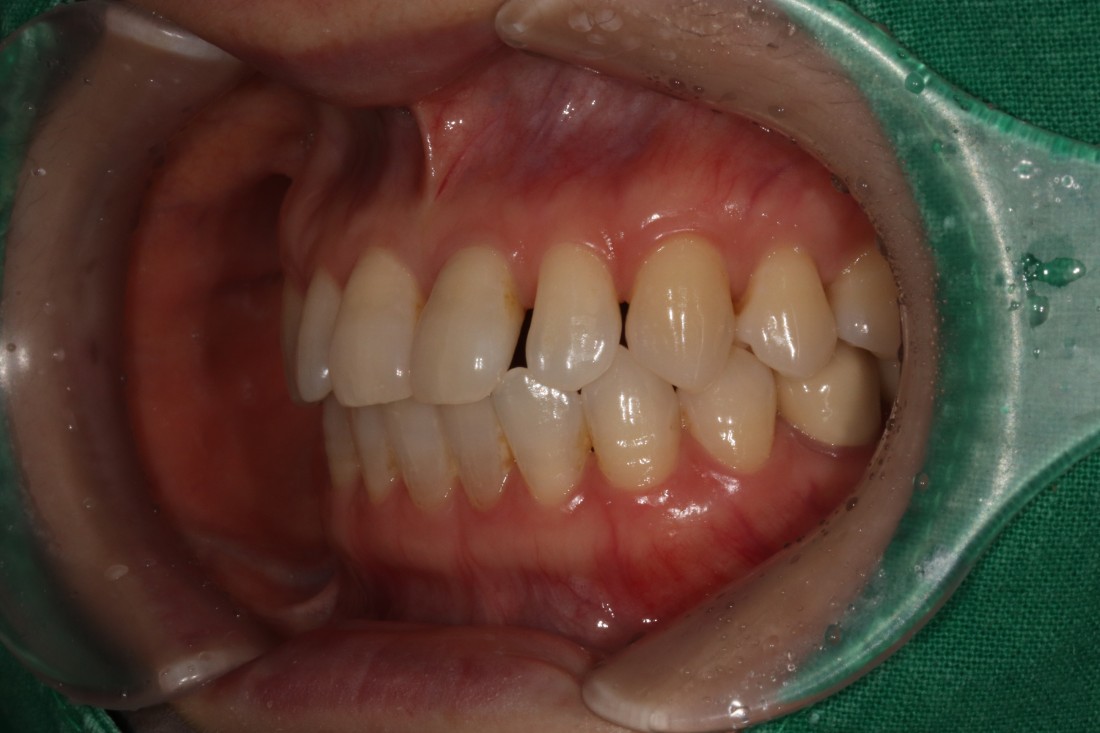

누가봐도 라미네이트 한 것 같은

뭉툭하고 새하얀 치아가 아니라,

광주 무삭제 라미네이트 치과는

'자연스러운 아름다움'을 추구합니다.

그렇기 때문에 20대부터 60대까지

정말 다양한 연령대의 고객님들이

지인 추천으로 방문해주시고 계신데요.

단순히 예뻐지기 위함이 아니라,

앞니 컴플렉스를 해결하고

치아의 기능적 요소까지 생각하여

불편함 없는 라미네이트 진료를 위해

노력하고 있습니다.